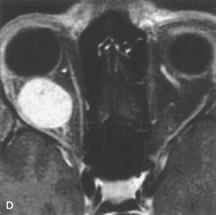

On MRI, uveal melanomas have a typical appearance that helps to differentiate them from other primary and secondary intraocular tumors as well as choroidal detachments. Pigmented melanomas are hyperintense on Tl-weighted images, hypointense on T2-weighted studies, and hyperintense on proton density–weighted examinations (Fig. 24).30,31,50,80–82 These signal characteristics have been attributed to the paramagnetic properties of melanin because of stable free radicals that shorten the T1 and T2 relaxation times. Moderate enhancement is seen on postgadolinium T2-weighted images. Gadolinium-enhanced T1-weighted images are particularly sensitive in detecting choroidal melanomas.83 MRI may be less sensitive in detecting extrascleral extension of tumor than echography performed by an experienced ultrasonographer.84

Fig. 24. A. T1- and (B) T2-weighted MR scans demonstrate a small nodular intraocular mass (arrows) that is very hyperintense on the T1-weighted scan and hypointense on the T2-weighted image. This signal intensity pattern is due to the presence of free radicals within melanin granules. C and D. Postcontrast fat-suppressed T1-weighted scans demonstrate homogeneous intense enhancement of the lesion and no evidence of seleral penetration or optic nerve invasion.